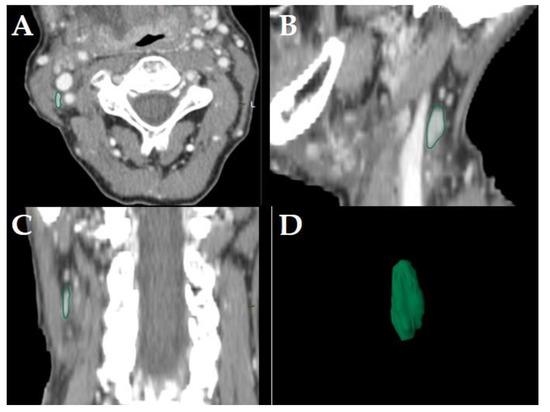

All diagnostic-, planning- and restaging-CTs were imported to the segmentation software (Elements, BrainLab, Munich, Germany). For each patient the three largest LNs were manually segmented in all data sets slice-by-slice in the axial plane using the “paint on slices” tool provided by the software. All segmented LNs were examined by two experienced, board certified head and neck radiologists with more than 15 years of clinical experience in head and neck CT reporting. The segmented LNs were classified as “pathologic” (Figure 2), “pathologic with ECS” (Figure 3) or “non-pathologic” (Figure 4), complying with current CT reading criteria for LN-malignancy [5,6,7].

Figure 4. Example of a LN classified as “non-pathologic” in a staging-CT of a 65-year-old, female HNSCC-patient with a tumor of the oral cavity staged cT4a cN2c cM0. Manually segmented LN in the axial plane (A); sagittal (B), coronal (C) reformatted views and three-dimensional rendering (D) of the LN are provided by the software. Neither central necrosis nor soft tissue infiltration nor irregular LN capsule were observed for this LN.

LNs were classified “non-pathologic” if in staging-, planning- or restaging-CT neither the criteria for malignancy [5,6] nor for ECS [7] were observed (Figure 4).

Consequently, the classification of the segmented LNs in “pathologic” (Figure 2), “pathologic with ECS” (Figure 3) and “non-pathologic” (Figure 4) by the two experienced head-and-neck-radiologists based on established criteria [5,6,7] was defined as reference.